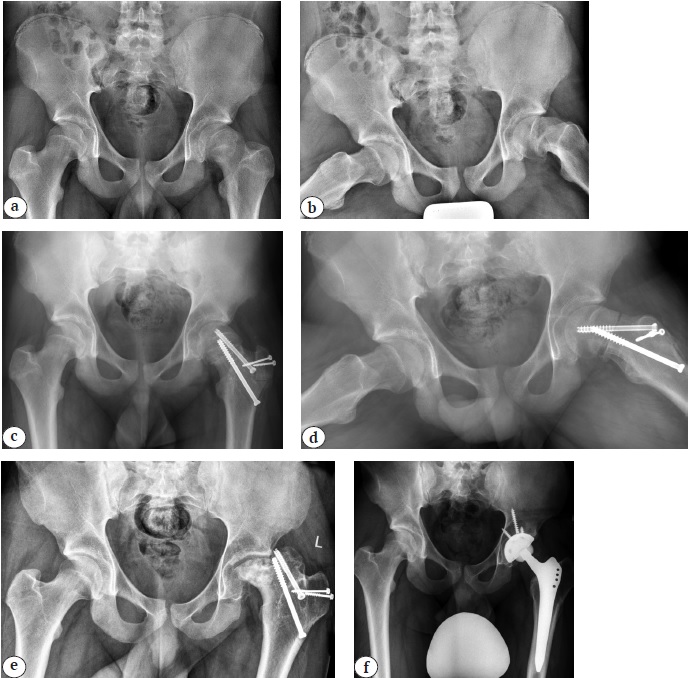

Рис. 4. История хирургических вмешательств у пациентки 14 лет: а — рентгенограмма тазобедренных суставов на момент первичного обращения к специалисту в возрасте 1 г. 7 мес. (дисплазия левого тазобедренного сустава IV–1 степени по дополненной классификации D. Tönnis [16]); b — ближайший результат хирургической реконструкции левого тазобедренного сустава (релюксация с выраженными дистрофическими явлениями в проксимальном отделе бедренной кости); c — повторная попытка стабилизации левого тазобедренного сустава (отсутствие концентрического вправления головки бедренной кости в вертлужную впадину, высокое положение большого вертела, мальпозиция металлоконструкций в виде их пенетрации в полость сустава); d, e — отдаленный результат хирургического лечения (тотальный лизис проксимального отдела бедренной кости, вертлужная впадина как анатомическая структура отсутствует, укорочение бедренной кости более 8 см, экстремально малые размеры канала бедренной кости и локации для имплантации чашки эндопротеза в анатомическую позицию); f — среднесрочный результат выполнения тотального бесцементного эндопротезирования системой Zimmer Biomet (чашка TMT® 38 мм; ножка Wagner cone® 13, пара трения: металл — поперечносвязанный полиэтилен) с применением техник остеотомии большого вертела по T. Paavilainen и дилятационной остеотомии бедренной кости

Fig. 4. Surgical interventions sequence of a 14-year-old patient: а — X-ray of the hip joints at the initial specialist visit at the age of 1 year and 7 months (grade IV-1 left-sided hip dysplasia according to the supplemented D. Tönnis classification [16]); b — short-term result of the left hip joint surgical reconstruction (reluxation with pronounced dystrophic changes in the proximal femur); с — a repeated attempt to stabilize the left hip joint (absence of concentric reduction of the femoral head into the acetabulum, a high position of the large trochanter, malposition of metal structures in the form of their penetration into the joint cavity); d, e — long-term result of the surgical treatment (total lysis of the proximal femur, acetabulum as an anatomical structure is absent, shortening of the femur bone over 8 cm, extremely small sizes of the femoral canal and the location for endoprosthesis cup implantation in the anatomical position); f — mid-term result of cementless THA performed with the Zimmer Biomet system (TMT® 38 mm cup; Wagner cone® 13, metal-crosslinked polyethylene), the T. Paavilainen techniques of greater trochanter osteotomy and dilated osteotomy of the femur